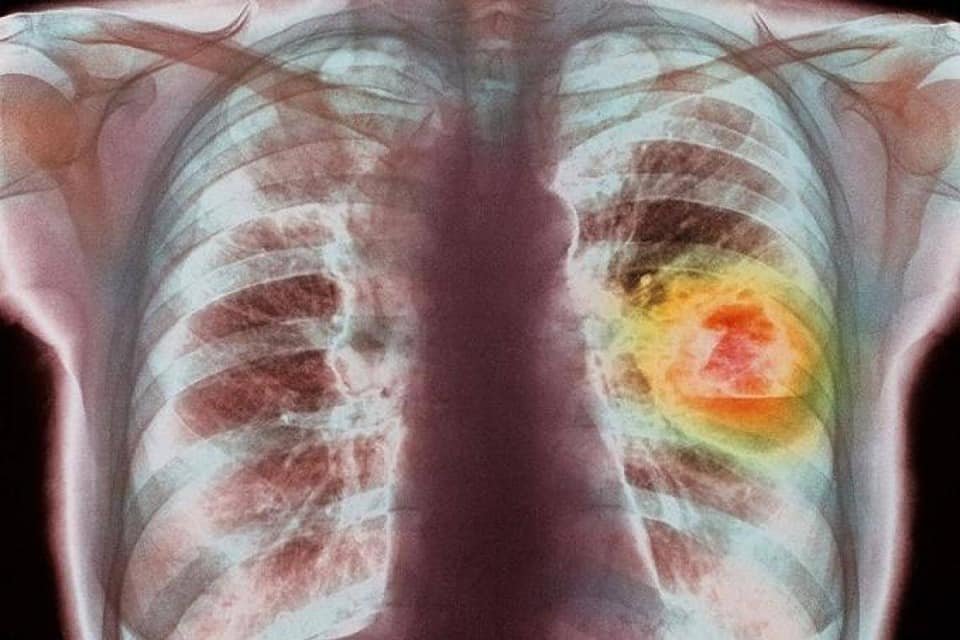

"ปอด" นับเป็นอวัยวะที่มีสำคัญมากในร่างกายของมนุษย์ ทำหน้าที่นำก๊าซออกซิเจนเข้าสู่ร่างกายและขับถ่ายก๊าซเสีย หรือก๊าซคาร์บอนไดออกไซด์ออกมา และยังเป็นอวัยวะที่เสี่ยงต่อการรับเชื้อโรคมากที่สุด โดยโรคในปอดที่พบบ่อยในผู้ป่วย คงหนีไม่พ้น “โรคปอดอักเสบ”

ผศ.นพ.ศิระ เลาหทัย ศัลยแพทย์ทรวงอกเชี่ยวชาญด้านผ่าตัดส่องกล้องโรงพยาบาลวชิรพยาบาล กล่าวให้ความรู้ว่า โรคปอดอักเสบ เป็นโรคที่มีการอักเสบของเนื้อปอด ซึ่งประกอบไปด้วยถุงลมปอดและเนื้อเยื่อโดยรอบมีอาการบวมขึ้น ทำให้ปอดทำหน้าที่ได้น้อยลงส่งผลอาการหายใจเหนื่อยหอบ หายใจลำบาก ในบางรายผู้ป่วยอาจมีอาการรุนแรงถึงขั้นเสียชีวิตได้ โดยเฉพาะอย่างยิ่งในกลุ่มเสี่ยง เช่น ผู้สูงอายุหรือผู้ที่มีภูมิต้านทานต่ำ ซึ่งถ้าตรวจพบในระยะแรกเริ่มจะสามารถรักษาให้หายได้ ซึ่งอาการแสดงและความรุนแรงของโรคจะแตกต่างกันไป และบางครั้งอาจพบปอดอักเสบเป็นภาวะแทรกซ้อนของโรคอื่นๆ ด้วย

สำหรับปอด เป็นอวัยวะในระบบทางเดินหายใจที่อยู่ภายในทรวงอกทั้ง 2 ข้าง ซึ่งมีลักษณะเป็นเนื้อหยุ่นๆ สีออกชมพู มีหน้าที่แลกเปลี่ยนก๊าซจากอากาศที่เราหายใจเข้าไป คือ ในช่วงหายใจเข้าปอดจะทำหน้าที่นำก๊าซออกซิเจนเข้าไปเลี้ยงร่างกาย และในขณะเดียวกันปอดจะขับก๊าซคาร์บอนไดออกไซด์ ซึ่งเป็นสิ่งที่ร่างกายไม่ต้องการออกมากับลมหายใจ ปกติเนื้อปอดจะเป็นอวัยวะที่ปราศจากเชื้อโรค เมื่อมีเชื้อโรคหรือสิ่งแปลกปลอมอื่น ๆ เข้าไปถึงเนื้อปอดจะส่งผลให้เนื้อปอดมีการอักเสบและมีการบวมเกิดขึ้น ในคนที่มีสุขภาพดีร่างกายจะมีระบบภูมิต้านทานโรคที่ดีที่จะช่วยขจัดเชื้อโรค และของเสียในทางเดินหายใจได้อย่างมีประสิทธิภาพหรือที่เรียกว่าการไอนั่นเอง แต่ในคนที่มีระบบภูมิคุ้มกันลดลง หากปอดติดเชื้อก็จะเกิดปอดอักเสบได้ง่ายขึ้นและมีโอกาสเกิดภาวะแทรกซ้อนตามมาได้